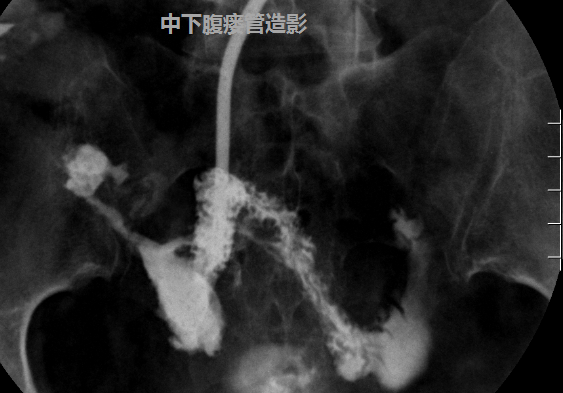

吴万庆副主任医师接诊后,详细了解病史及查体,经过造影及CT检查,确定瘘口的部位及腹腔脓腔情况,发现患者腹壁有三个瘘口,粪便外渗,诊断考虑为克罗恩病并发肠瘘。